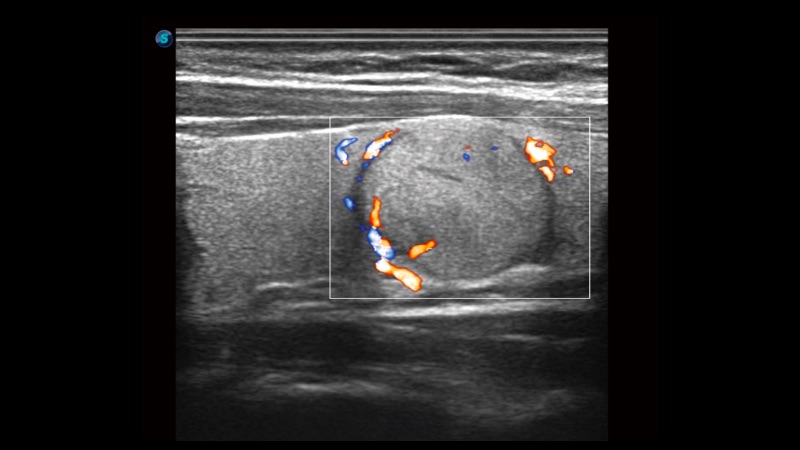

凸陣、線陣和相控陣探頭進(jìn)行實時掃描時,開啟擴(kuò)展成像模式,可以擴(kuò)展超聲圖像視野,以便更完整地查看大的病灶或組織器官的解剖結(jié)構(gòu)。

通過色彩血流和實時寬景相結(jié)合,可觀察到完整的靜脈或動脈的血流,方便醫(yī)生檢查。實時掃查過程中,如有任何操作失誤也可以很容易地進(jìn)行回掃擦除,而不會中斷掃查。